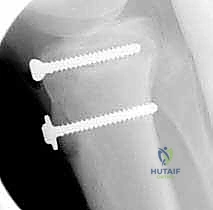

5. التثبيت الداخلي (Internal Fixation)

هنا تبرز مهارة الجراح في اختيار طريقة التثبيت التي لا تضر بصفيحة النمو (إذا كانت لا تزال مفتوحة).

* استخدام البراغي المجوفة (Cannulated Screws): يتم إدخال سلك توجيهي رفيع أولاً، وبعد التأكد من موقعه بالأشعة السينية داخل غرفة العمليات، يتم إدخال برغي أو برغيين من التيتانيوم القوي فوق السلك لتثبيت العظم. يحرص الدكتور هطيف على توجيه البراغي من الأمام إلى الخلف، وفي بعض الأحيان بزاوية مائلة لتجنب اختراق صفيحة النمو قدر الإمكان.